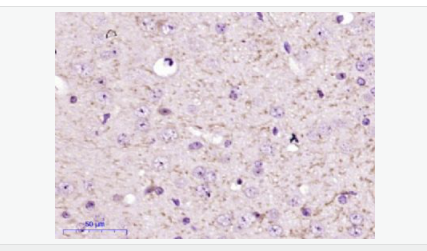

| 產(chǎn)品介紹 | FBXO2 is a 296 amino acid protein that contains one F-box domain and one F-box associated domain. Functioning as a component of the SCF complex, FBXO2 is thought to recognize and bind to select phosphorylated proteins, thereby promoting their ubiquitination and subsequent degradation. Function: Substrate recognition component of a SCF (SKP1-CUL1-F-box protein) E3 ubiquitin-protein ligase complex that mediates the ubiquitination and subsequent proteasomal degradation of target proteins. Involved in the endoplasmic reticulum-associated degradation pathway (ERAD) for misfolded lumenal proteins by recognizing and binding sugar chains on unfolded glycoproteins that are retrotranslocated into the cytosol and promoting their ubiquitination and subsequent degradation. Prevents formation of cytosolic aggregates of unfolded glycoproteins that have been retrotranslocated into the cytosol. Able to recognize and bind denatured glycoproteins, preferentially those of the high-mannose type. Subunit: Component of the SCF(FBXO2) complex consisting of CUL1, RBX1, SKP1 and FBXO2. Predominantly detected as heterodimer with SKP1; the heterodimer with SKP1 is not part of the SCF(FBXO2) complex (By similarity). Subcellular Location: Cytoplasm. Microsome membrane. Similarity: Contains 1 F-box domain. Contains 1 FBA (F-box associated) domain. SWISS: Q9UK22 Gene ID: 26232 Database links: Entrez Gene: 26232 Human Entrez Gene: 230904 Mouse Omim: 607112 Human SwissProt: Q9UK22 Human SwissProt: Q80UW2 Mouse Important Note: This product as supplied is intended for research use only, not for use in human, therapeutic or diagnostic applications. |